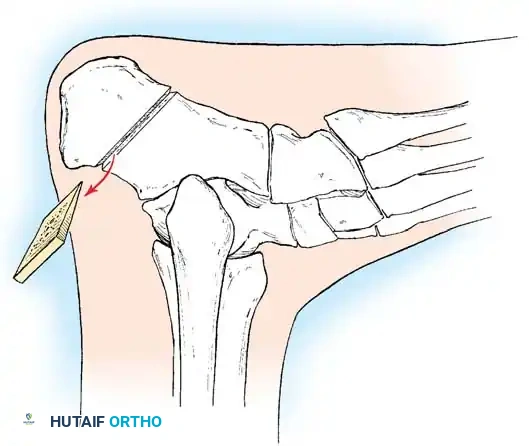

1. Lateralizing Calcaneal Osteotomy (Dwyer or Sliding)

* Indications: Fixed hindfoot varus with a preserved, non-arthritic subtalar joint.

* Approach: Oblique lateral incision posterior to the sural nerve and peroneal tendons.

* Osteotomy: A lateral closing-wedge (Dwyer) or a lateral sliding step-cut osteotomy is performed using an oscillating saw.

* Translation: The posterior tuberosity is translated laterally by 10 to 15 mm and rotated out of varus.

* Fixation: Secure with one or two large-fragment (6.5 mm or 7.3 mm) cannulated screws directed from the posterior heel into the anterior calcaneus.